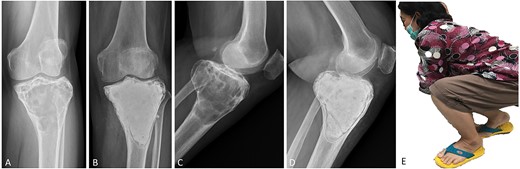

(A, C) Case no. 7: female, 54 years of age with GCTB at the proximal tibia with subchondral bone involvement, Campanacci grade III. (B, D) Radiograph at 58 months after extended curettage with hydrogen peroxide, phenol, and cementation. (E) MSTS score 86%.